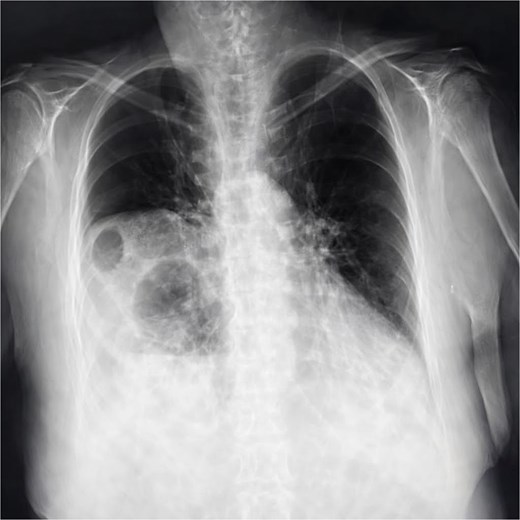

Chest X-ray (Fig. 1) showed elevation of the right hemidiaphragm, diaphragmatic eventration, obliteration of the left subdiaphragmatic recess, and a subdiaphragmatic colonic air-fluid level. Computed tomography (CT) (Fig. 2) confirmed a large right anterolateral diaphragmatic hernia with a craniocaudal extent of ~16 cm and a hernia neck measuring 2 × 5 cm. Measurements were obtained from multiplanar CT reconstructions and reflected the hernia sac size and defect width. A small left-sided fat-containing diaphragmatic hernia (collar 12 mm) and a right uncomplicated inguinal hernia containing distal ileum were also identified.

Chest X-ray showing elevation of the right diaphragmatic cupola, eventration (blue arrow), obliteration of the left subdiaphragmatic recess and sub diaphragmatic colonic air fluid level.